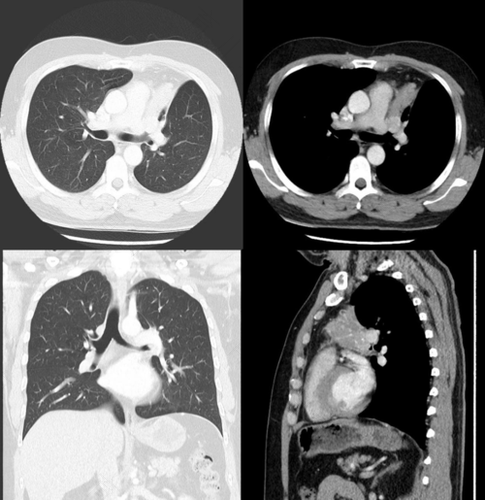

支气管狭窄属于很常见的气道疾病,而支气管的变窄,通常是因为支气管里面长了良性、恶性肿瘤,或者是出现了炎性肉芽肿,这就会使气道狭窄,而且还会有气道附近的占位性病变,进而使患者出现一些不良症状。

在支气管变窄之后,患者就会出现喘鸣、咳嗽以及痰多的症状。尤其是在进行体力活动的时候,就会有分泌物增多的情况。如果患者以前做过气管切开或者是插管术的话,现在出现了以上症状,大多是因为气管瘢痕狭窄导致的。

支气管变窄大多都属于良性狭窄,通常都是使用支气管球囊扩张来进行治疗。要是患者属于短暂性狭窄,例如由于气管进入了异物而导致的狭窄,只要将异物取出后,气管便能够很快的恢复正常。如果是恶性狭窄的话,比如气管长了肿瘤,治疗起来就比较麻烦了,通常都需要进行手术。